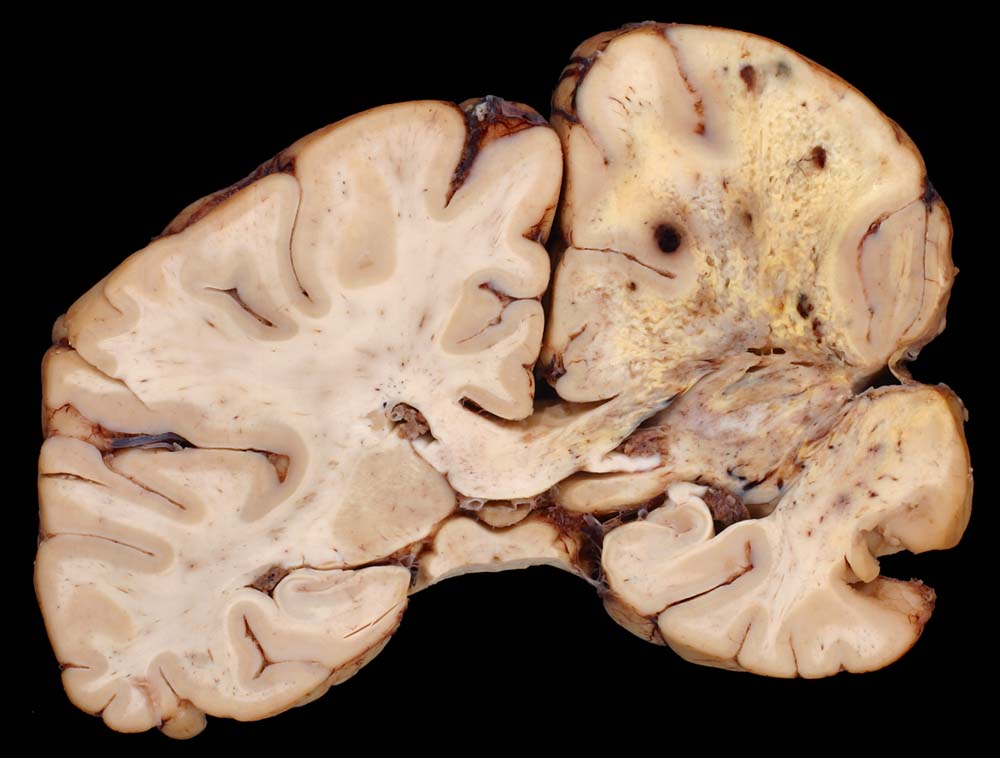

Lokalisation:

Bevorzugte Lokalisationen sind das Marklager des Frontal- und Temporallappens. Glioblastome des Hirnstammes sind selten und betreffen meist Kinder. Von dort breiten sie sich oft über den Balken schmetterlingsförmig auf die Gegenseite aus. Weniger als 5% der Tumoren wachsen multizentrisch. Eine Aussaat in den Subarachnoidalraum mit Metastasierung über den Liquor findet sich selten. Noch rarer sind hämatogene Metastasen in extraneurale Organe.

Morphologie:

Die Schnittfläche ist auffallend bunt. Dies ist bedingt durch ein Nebeneinander von graurotem vitalem Tumorgewebe, gelben Nekrosen, roten Einblutungen und gelegentlich grünlichen Gallertzysten.